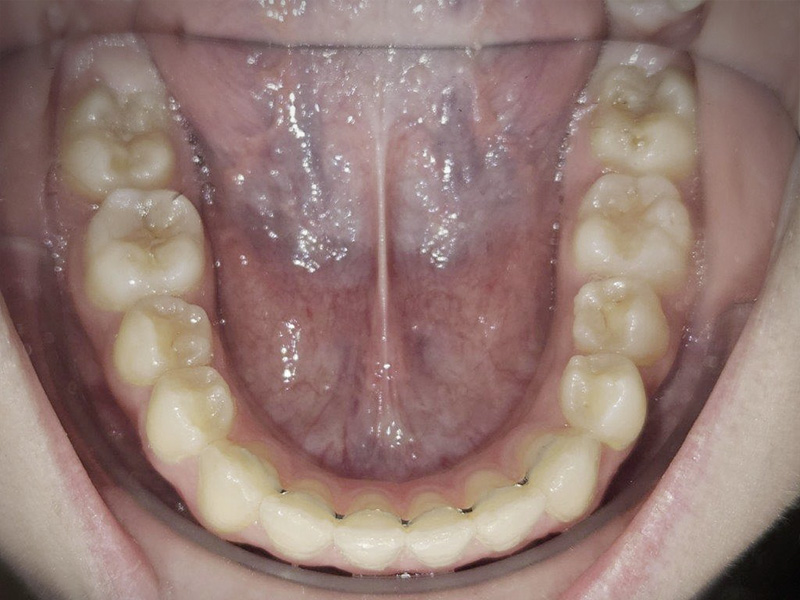

- >Contention

Après un traitement d’orthodontie (par bagues ou par gouttières), les dents mettent une année pour retrouver une certaine stabilité.

Nous installons donc des systèmes pour que les dents bougent le moins possibles, un peu comme un tuteur avec une plante.

Malgré la contention, les dents peuvent tout de même se déplacer de nouveau, ce qui nécessite une surveillance au cabinet d’au moins 3 ans.

Au cabinet, nous utilisons très souvent la technologie MEMOTAIN.

Il s’agit d’un fil de contention ajusté, confortable, individualisé grâce à l’empreinte optique et conçu sur mesure au laboratoire afin de s’adapter de manière personnalisée à chacun.